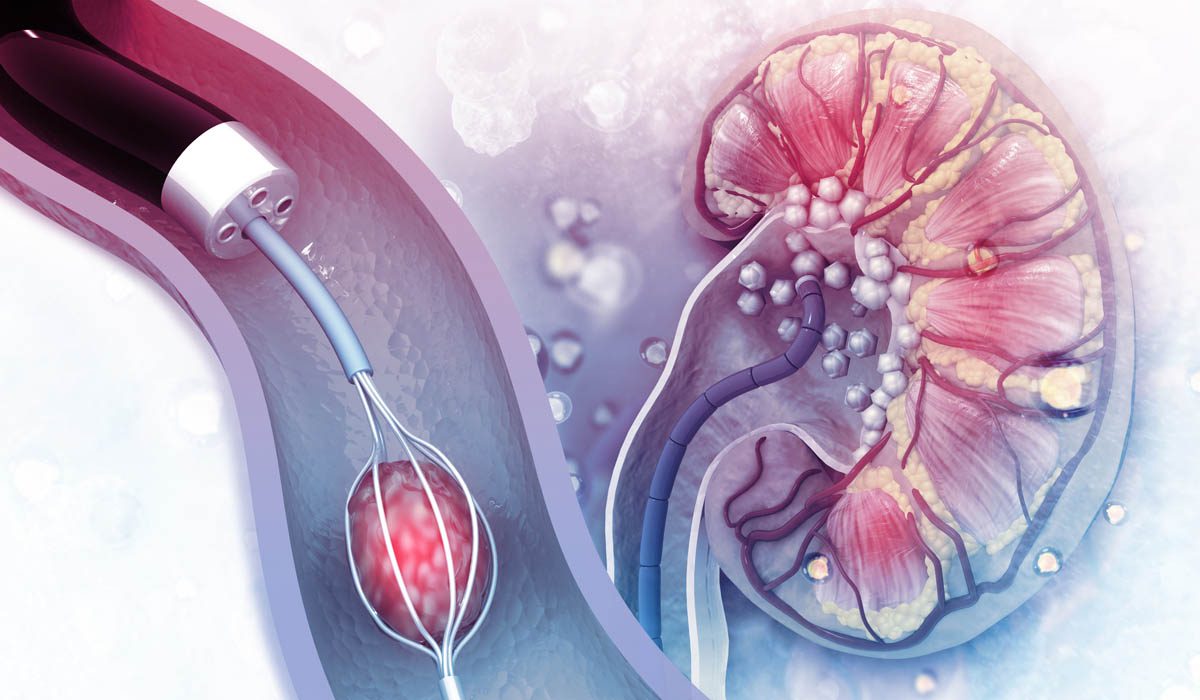

General surgeon for spleen removal in Thane Dr. Ankur Bhanushali General and Advanced Laparoscopic Surgery General surgery is a diverse specialty in medicine that addresses various surgical conditions involving the abdominal organs and soft tissue masses in the extremities. With advancements in medical technology, many procedures can now be performed using minimally invasive techniques. This approach, often called laparoscopic or "keyhole" surgery, involves operating through small incisions rather than traditional large ones. Most abdominal and thoracic procedures can now be carried out effectively using laparoscopic techniques. Types of Procedures: Abdominal Wall Reconstruction Surgery Appendectomy Open appendectomy Laparoscopic appendectomy Gallbladder Surgery Open cholecystectomy Laparoscopic cholecystectomy Thyroid Surgery Hernia Repair Perineal Surgeries Treatment of piles (open and stapled procedures) Fissures, fistulas, and perineal abscesses Pilonidal Sinus Surgery Includes flap reconstruction Tuberculosis-related Surgeries Laparoscopy-assisted laparotomy for small intestine tuberculosis Removal of Cysts and Soft Tissue Masses Breast Surgeries Management of fibro adenomas, fibrocystic disease, tumors, and breast cancer Lymph Node and Neck Mass Surgeries Biopsies and mass excisions Laparoscopic Solid Organ Surgeries Procedures include laparoscopic splenectomy, adrenalectomy, and parathyroid tumor removal What is Laparoscopic Surgery? Laparoscopic surgery uses a slender device called a laparoscope, which is equipped with a camera. This device is inserted into the abdominal or thoracic cavity through small incisions (usually 5 mm in size) using specialized ports. The camera transmits real-time images to a monitor, allowing surgeons to view and operate on internal structures with precision. This approach enables surgeons to perform the same procedures traditionally done through open surgery but with less disruption to surrounding tissues. Benefits of Laparoscopic Surgery: Smaller Incisions: Minimizes tissue damage. Reduced Pain: Patients experience less post-operative discomfort. Faster Recovery: Promotes quicker return to daily activities. Shorter Hospital Stays: Many procedures allow same-day discharge. Minimal Scarring: Results in either no visible scars or very small ones. Early Mobility: Patients can often move around the same day as their surgery. Best General Surgeons In Thane Best General Surgeons In Thane West, Thane Best General Surgeon in Thane - General Surgery Doctor Top General Surgeons in Thane West, Thane General Surgery and Minimal Access Surgery in Thane Best General Surgeons in thane west thane Best General Surgeons in Thane West Best General Surgeons in Thane General Surgeon Thane General Surgeon in Jupiter Hospital Thane General Surgeon in Bethany Hospital Thane Laparoscopic Surgeon in Thane General Surgeon near me Best Surgeon near me Jupiter Hospital surgeons General Surgeon in Mumbai